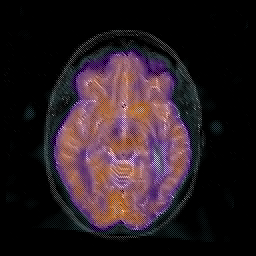

Glioblastoma multiforme overlay -- Slice #24

[Home][Help][Clinical][Tour 1][Tour 2][Tour 3] Slice 24